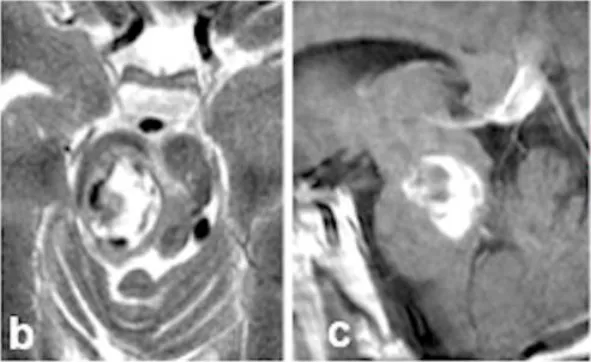

此次出血导致严重临床后果。新发出血引发左侧肢体轻偏瘫和感觉减退,右侧外展神经及面神经麻痹,伴随意识水平下降。术前MRI清晰显示22mm出血性病灶(图b-c)向尾侧延伸(图c),将患者置于生命危险境地。